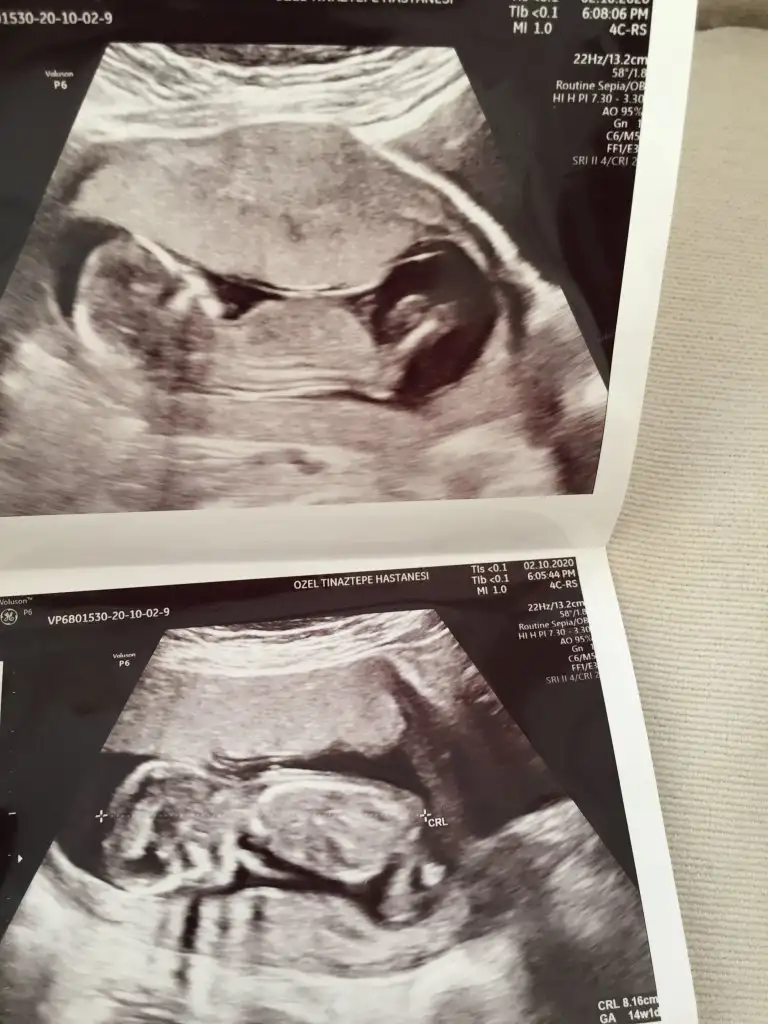

Kızlar selam devlete gittim ama rezalet resmen sağlam giren hasta çıkar o dereceydi bakmadı bile bir kafasına baktı okdr 14hafta erken belli olmaz dedi ben tabi duramadım hemen özelden başka doktordan randevu aldım oda 14de gelince niye ara dönemde geldin cinsiyet için dimi kendi doktorunuzu bekleseniz diye fırçaladımı

neyse baktı etti dedi kız gibi ama net göremiyorum yüzüstü duruyor dedi ama net kız diyemem dedi bekle 16yı dedi sağolun dedim

bekleyin kızlar gibilerle kafa daha çok karışıyor bide siz bakin bakim fikriniz ney☺